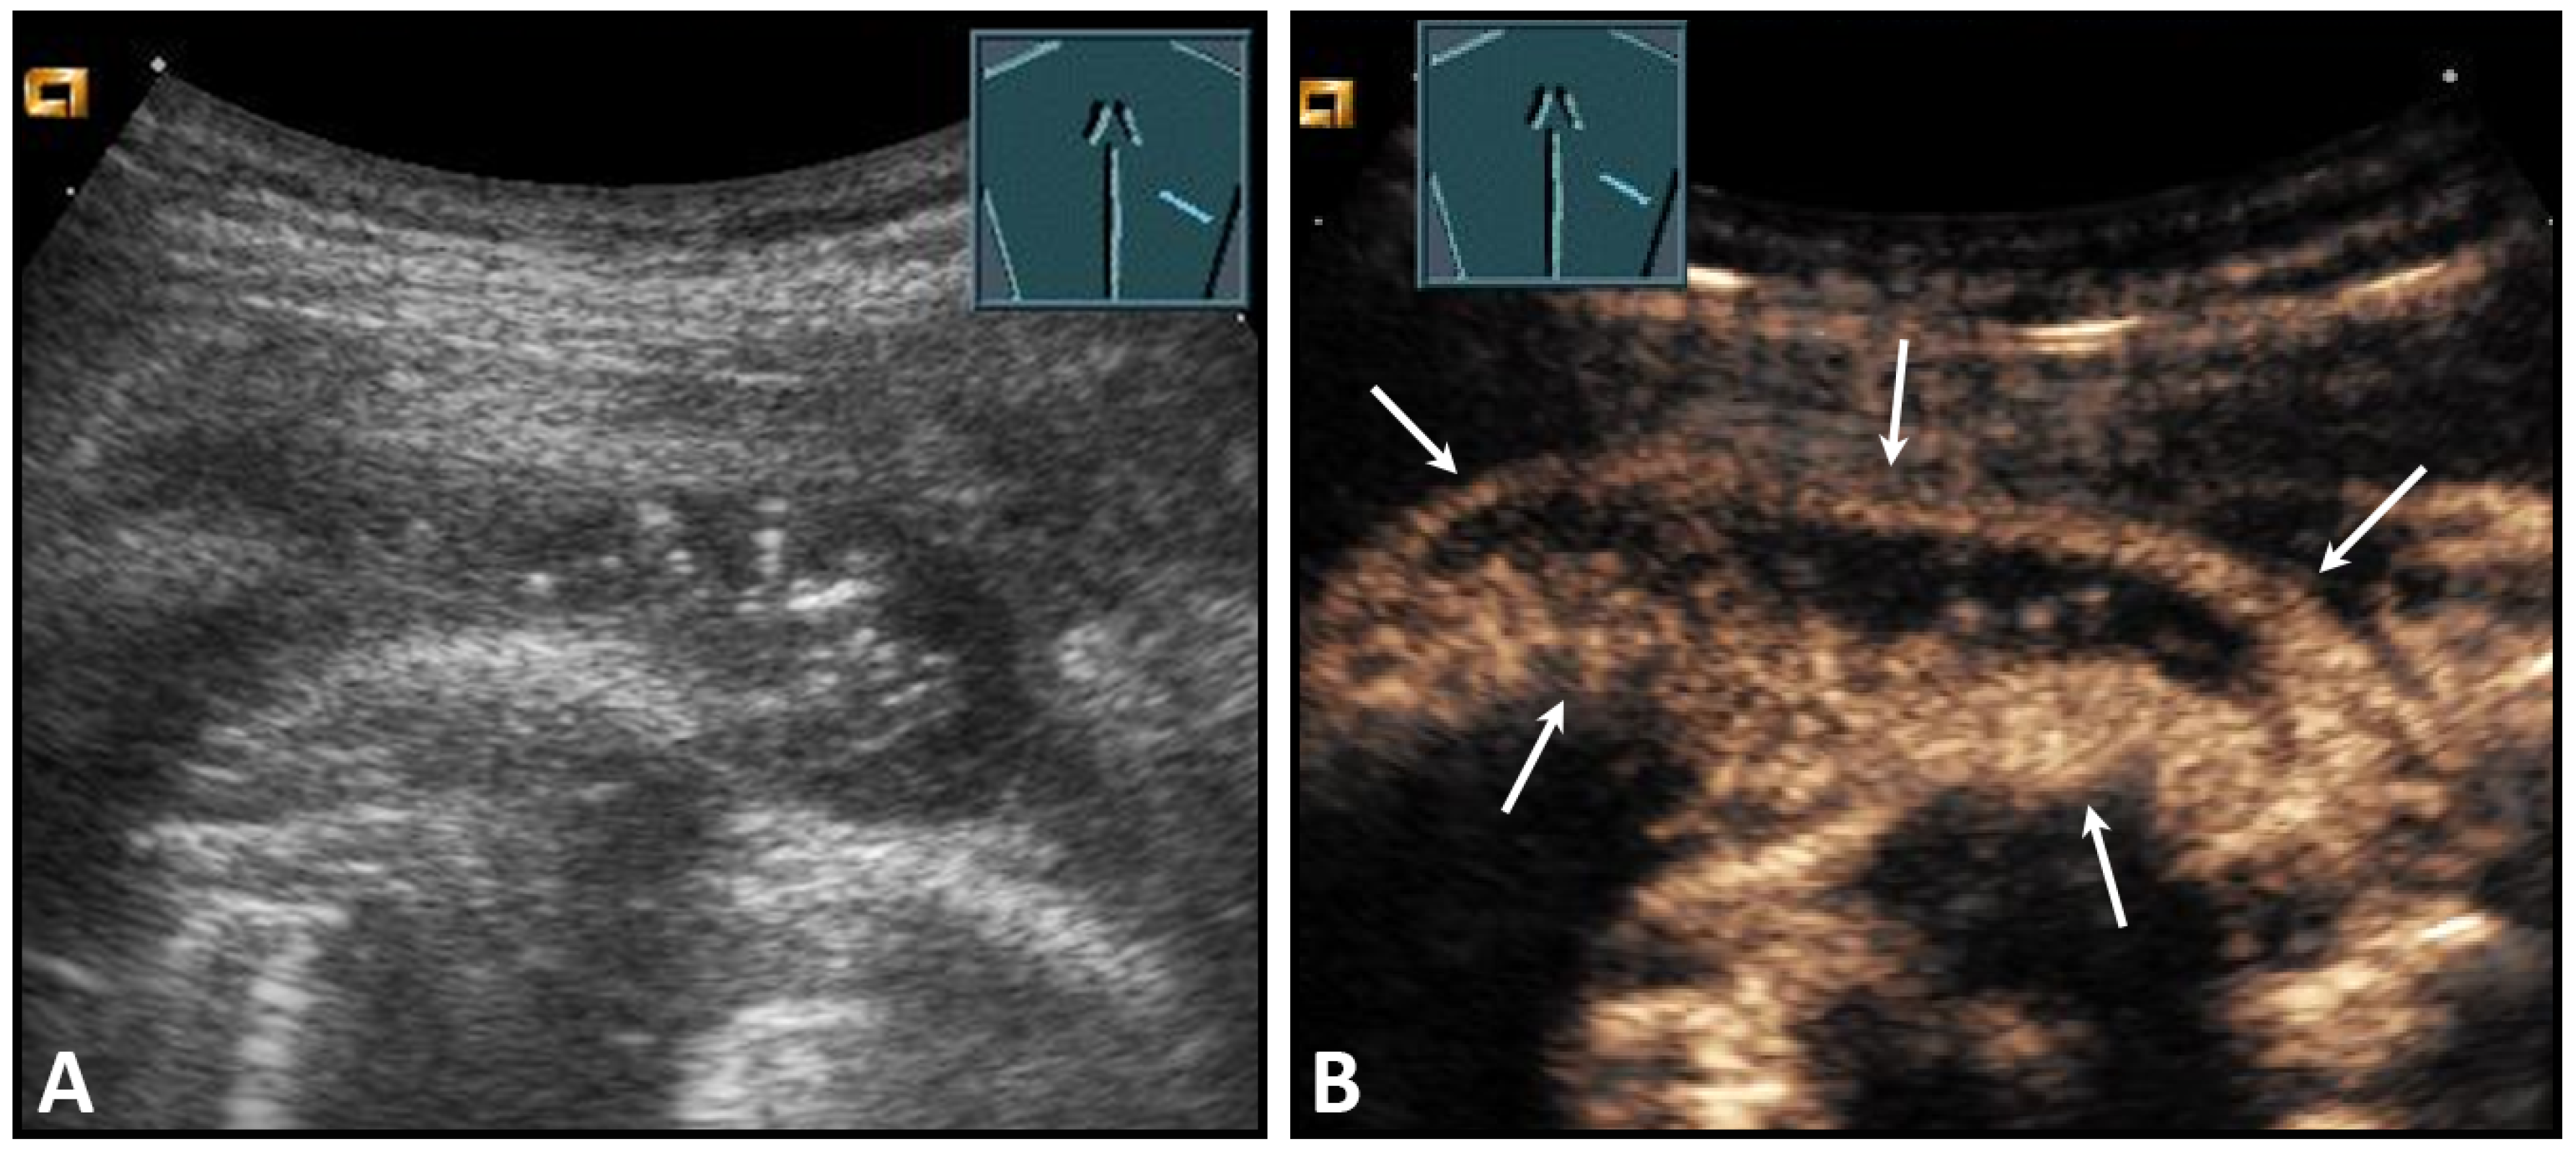

The most common tumors of the chest wall are lipomas, which manifest clinically as a painless and soft swelling, preferentially in adipose patients, usually between the ages of 50 and 70 years [15]. The sonomorphology is variable. In most cases (28–60%), lipomas present as a sharply localized, poorly vascularized, soft mass with an echo texture that is nearly indistinguishable from the surrounding adipose tissue. However, lipomas may also be more echoic (20–52%) or less echoic than the surrounding adipose tissue (20%) (Figure 5) [16,17].

Figure 5.

A dorsal chest wall mass with a soft echogenic subcutaneous mass consistent with lipoma (A). The echotexture of the lipoma is similar to that of the surrounding adipose tissue (B).